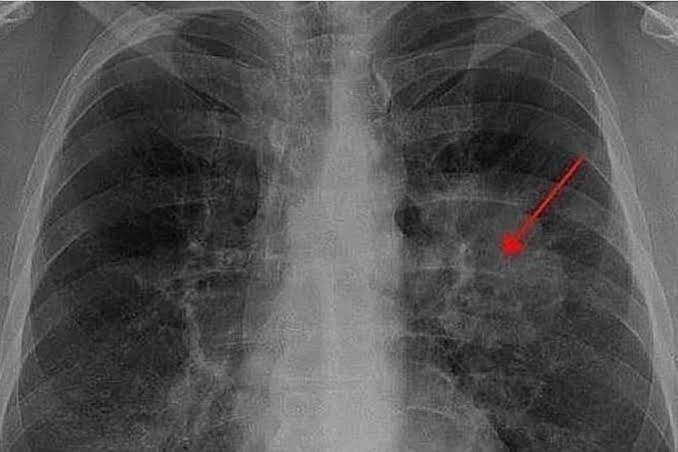

La importancia de esta conmemoración radica en que el cáncer de pulmón representa una de las principales causas de muerte por neoplasias tanto en hombres como en mujeres en México. A través de esta fecha, se busca informar a la población sobre los principales factores de riesgo —entre los que destacan el tabaquismo, la exposición al humo de leña o carbón y la contaminación ambiental— y promover estilos de vida saludables. Asimismo, se enfatiza la relevancia de la detección oportuna, ya que en muchas ocasiones los síntomas aparecen en etapas avanzadas, dificultando el tratamiento y reduciendo las probabilidades de recuperación.

Más allá de la sensibilización, este día sirve para reafirmar el compromiso del sistema de salud y de la sociedad para garantizar un diagnóstico temprano y un acceso equitativo a tratamientos especializados. Recordar esta fecha es también un homenaje a quienes luchan contra la enfermedad y a sus familias, recordando que la prevención es la herramienta más poderosa y que la detección a tiempo puede salvar vidas.